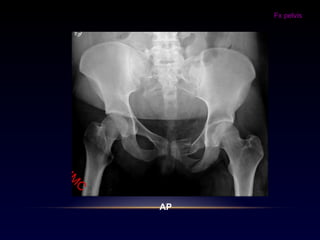

Fx pelvis

Trauma de alta energía jóvenes – adultos

Trauma de baja energía ancianos

AP

ENTRADA

SALIDA